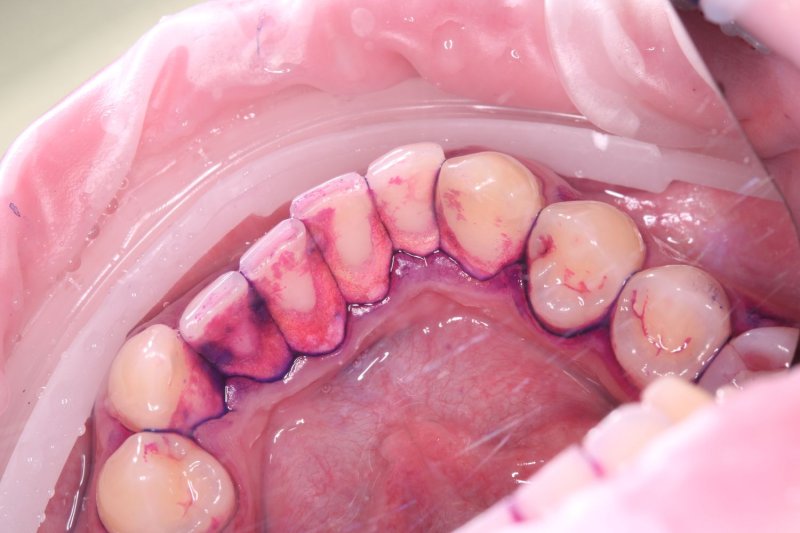

До

professionalnaya-gigiena-gbt-protokol-do

Воспаление и болезненность десен, наличие мягкого налета и твердых зубных отложений (зубного камня), являющихся основной причиной воспалительного процесса.

Проведение чистки по современному швейцарскому протоколу Guided Biofilm Therapy (GBT), включающему контролируемое удаление биопленки, зубного камня и полировку зубов.